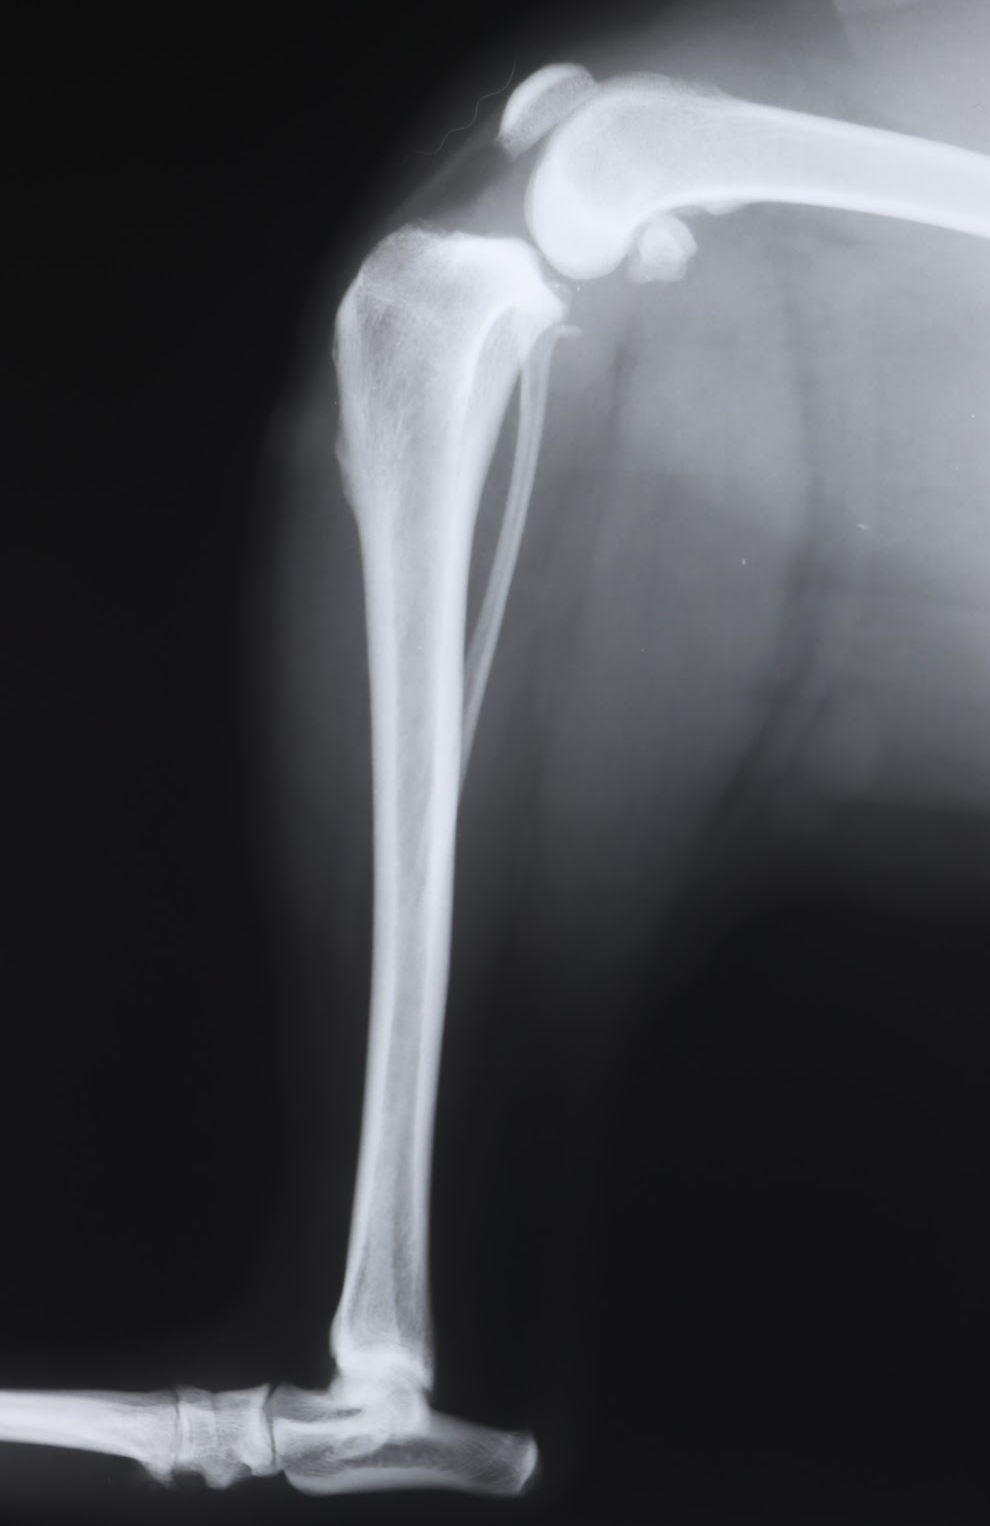

犬の前十字靭帯断裂の手術には、主にTPLOとLSSという2つの方法があります。TPLOは、脛骨の高平部を切断し、角度を変えることで膝関節の安定性を高める手術です。一方、LSSは、膝の外側に糸を通し、関節の安定性を図る手術です。

今回、当院で手術したのは、35kgのピットブルという大型犬で、体重も重く、活動量も高いということもあり、LSSは通常、適応外の手術となります。しかも肥満犬です。本来は高度医療施設でのTPLOをするのが最良です。(当院でTPLOを行っておらず、LSSは対応しています)

通常、LSS手術後にはギプス固定は行いませんが、今回の症例では、手術の成功率を高めるために、術後にギプス固定を行うという、やや特殊な方法を選択しました。これは、LSSが大型犬に適さないというリスクを補うため、術後の関節の安定性を高めることを目的としたものです。また、ピットブルのような筋肉質な犬種は、術後の関節の動きが大きくなりやすく、ギプス固定によって過度の動きを抑制することで、関節への負担を軽減する効果も期待できます。

LSSの治癒原理は、膝関節の脇に糸をかけ、ももとすねの骨の位置を適した位置で安定化させ、その後自然に起こる関節内や縫合糸の周囲の線維化を利用し、継続的な安定化を得るというものです。糸はしばらくするとゆるむので、恒久的な靭帯の代わりにはなりません。どんな手術方法でも切れた靭帯はつなげることはできません。線維化で安定化させるには、しばらくの間ギプス固定が有効であると考えます。よって、治癒原理を考えれば、一般的な小型犬においても、LSSのあとにはギプス固定は適しているかもしれません。

手術は無事に終了し、一ヶ月ほどギプス固定を行った結果、順調に回復しました。